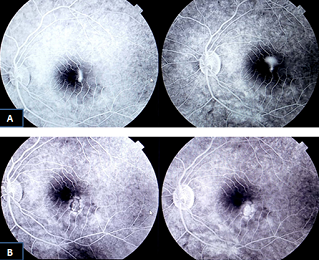

This study was designed to evaluate the efficacy of low-dose of oral acetylsalicylic acid (aspirin) with focal argon laser for the treatment of acute central serous chorioretinopathy (CSCR). In this prospective case-control study, 40 Patients with acute CSCR were classified randomly to two groups; group A with no treatment as the control group and group B with argon Laser in focal treatment once, followed by aspirin, 100 mg per day orally, with follow up period of 12 months by evaluation of visual acuity, and by Optical Coherence Tomography (OCT) Â every three months for one year. Patients in second group treated with argon Laser and aspirin showed more clinically significant improvement in both visual acuity and OCT macular thickness by the end of follow up period when compared with the observational group. It was concluded that argon Laser with low-dose oral aspirin results in improvement of visual acuity and OCT macular thickness.